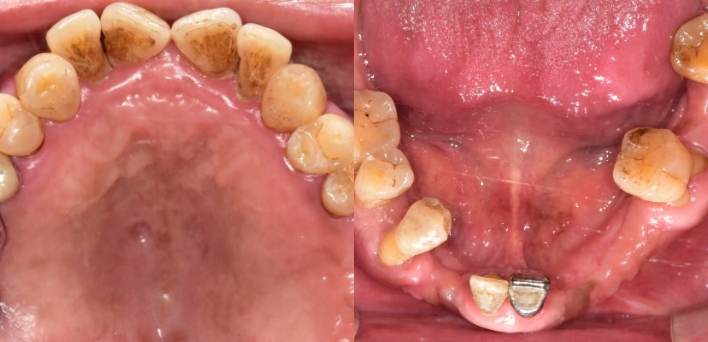

임플란트 케이스

임플란트 Before & After

The seoul dental clinic

치료 기록 더보기버튼

※ 더서울치과의원은 의료법을 준수하며 위 케이스는 실제 환자의 동의를 얻은 사례로 치료 전, 후가 동일한 환경에서 촬영되었습니다.

환자 케이스에 따라 부작용이 발생할 수 있습니다. 이 부분은 의료진의 충분한 상담과 체크를 통해 예방하고 줄일 수 있습니다.

[임플란트 부작용] 수술 후 관리가 소홀할 경우 출혈, 주위염 등의 부작용이 발생할 수 있어 구강 위생을 철저히 유지하고, 정기적인 검진을 통해 상태를 점검하는 것이 중요합니다.